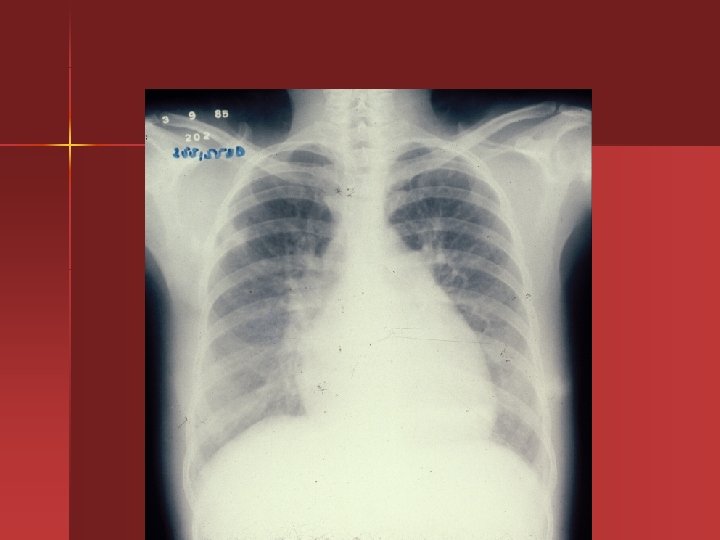

Estenosis Mitral Diagnostico Auscultacion: Ritmo de Duroazier n Electrocardiograma: “onda P mitral” n Rx con crecimiento de auricula y orejuela izquierda, congestion venocapilar. n Ecocardiograma , Doppler n Angiografia n